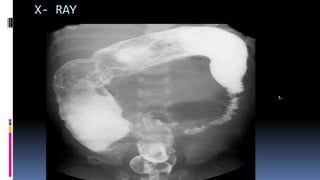

1) Plain abdominal X-ray- to see intestinal obstruction

X- RAY

1.